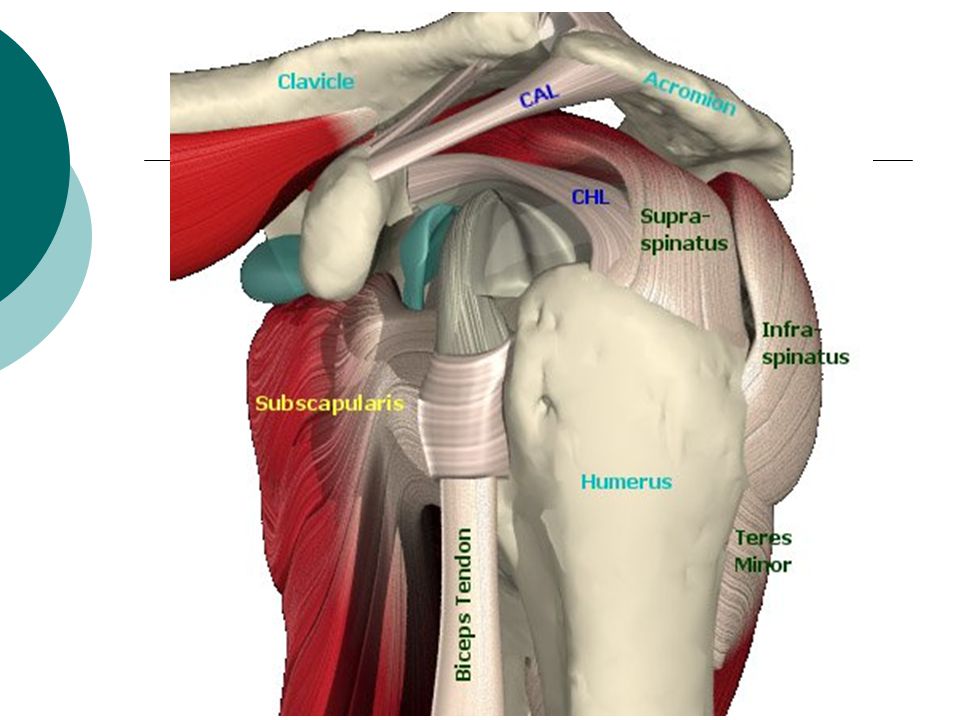

Фотографии мышц ротаторной манжеты плеча